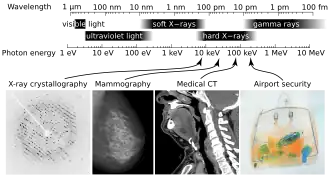

Рентге́новское излуче́ние — электромагнитные волны, энергия фотонов которых лежит на шкале электромагнитных волн между ультрафиолетовым излучением и гамма-излучением (от ~10 эВ до нескольких МэВ), что соответствует длинам волн от ~103 до ~10−2 Å (от ~102 до ~10−3 нм)[1].

Энергетические диапазоны рентгеновского излучения и гамма-излучения перекрываются в широкой области энергий. Оба типа излучения являются электромагнитным излучением и при одинаковой энергии фотонов — эквивалентны. Терминологическое различие лежит в способе возникновения — рентгеновские лучи испускаются при участии электронов (либо связанных в атомах, либо свободных) в то время как гамма-излучение испускается в процессах девозбуждения атомных ядер. Фотоны характеристического (то есть испускаемого при переходах в электронных оболочках атомов) рентгеновского излучения имеют энергию от 10 эВ до 250 кэВ, что соответствует излучению с частотой от 3⋅1016 до 3⋅1019 Гц и длиной волны 0,005—100 нм (общепризнанного определения нижней границы диапазона рентгеновских лучей в шкале длин волн не существует). Мягкое рентгеновское излучение характеризуется наименьшей энергией фотона и частотой излучения (и наибольшей длиной волны), а жёсткое рентгеновское излучение обладает наибольшей энергией фотона и частотой излучения (и наименьшей длиной волны). Жёсткое рентгеновское излучение используется преимущественно в промышленных целях. Условная граница между мягким и жёстким рентгеновским излучением на шкале длин волн находится около 2 Å (≈6 кэВ)[1].